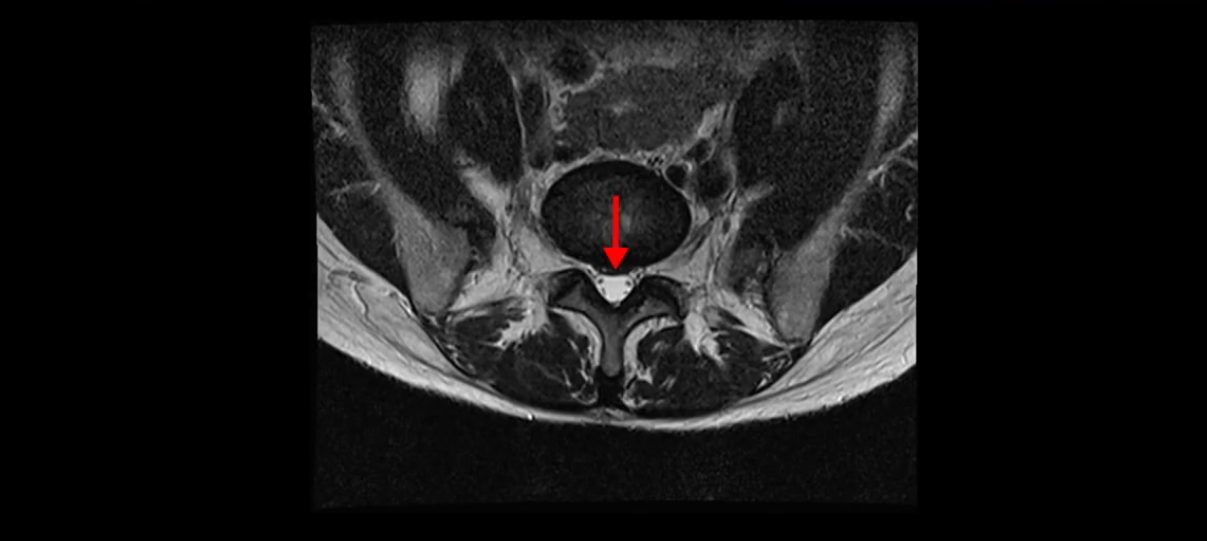

이분 MRI를 보시면 두 마디의 퇴행성디스크가 있습니다. 그리고 디스크가 조금씩 밀려 나와 있고요. 그런데 디스크 탈출 정도는 두 마디 다 심하지 않습니다. 4번 5번에는 디스크 탈출이 약간 있고,

척추관협착도 약간 진행이 되고 있고요.

5번 1번은 디스크 탈출이 가운데 쪽으로 살짝 있습니다.

또한 양쪽 신경 가지가 빠져나가는 추간공은 매우 넓은 상태입니다.

중요한 것은 이 정도 경미한 탈출과 협착으로는 양쪽 다리가 저리고 아플 수가 없습니다.

이분 MRI를 보시면 퇴행성디스크가 있고 약간의 협착이 있지만 이 정도의 퇴행성디스크와 협착으로는 신경이 눌려서 양쪽 다리가 저리고 아픈 증상이 나올 수가 없습니다. 그래서 MRI와 이 환자분의 다리 증상이 매치가 안 된다고 하는 의사들이 많은 겁니다.